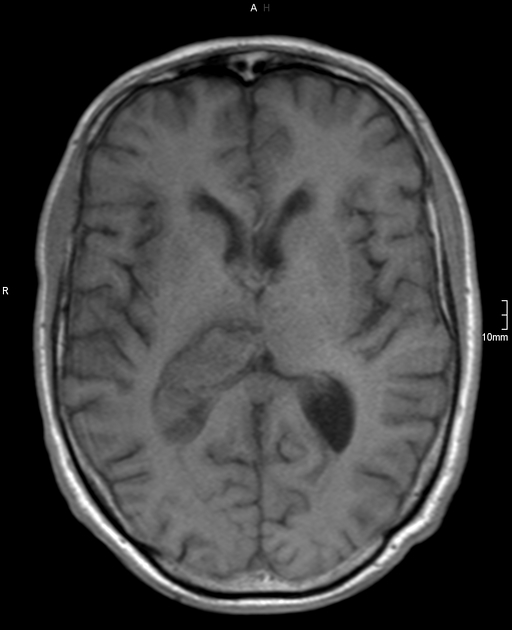

تشخیص خونریزی مغزی در MRI

خونریزی مغزی در ام آر آی و فازهای مختلف زمانی